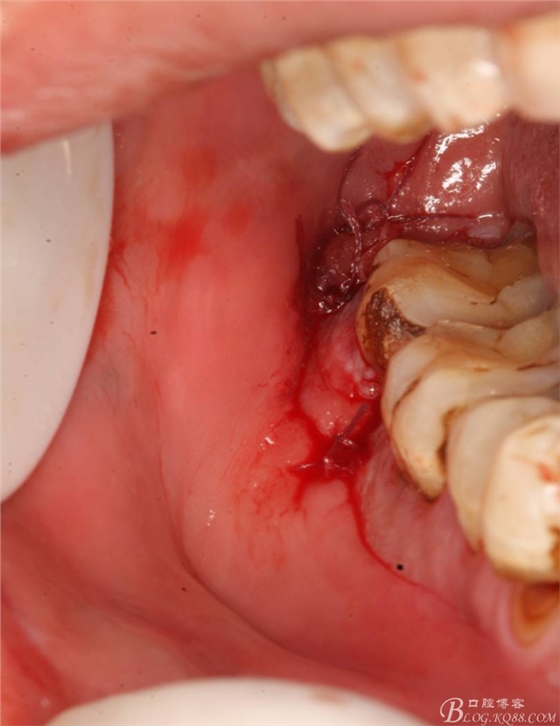

48未萌出,47遠(yuǎn)中可探及深約7mm的牙周袋。頰側(cè)47、48之間牙齦紅腫,有少量血性滲出。X線根尖片顯示:48牙冠反轉(zhuǎn)倒置,47遠(yuǎn)中牙槽骨吸收明顯。CBCT顯示:48牙冠近中面位于下頜管內(nèi)。

2.切開翻瓣

3.去骨、暴露48.